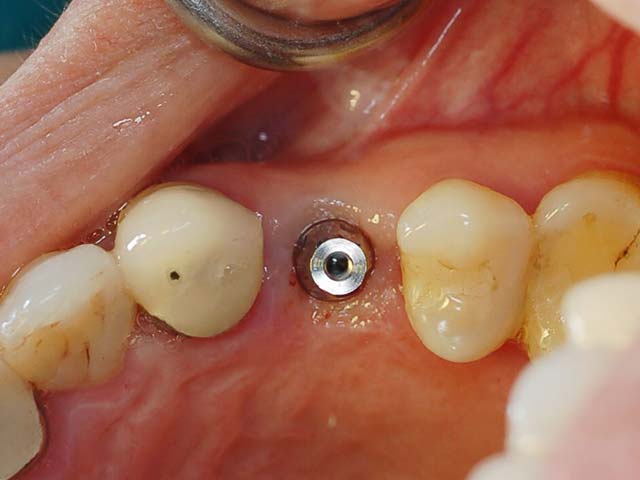

完成植牙